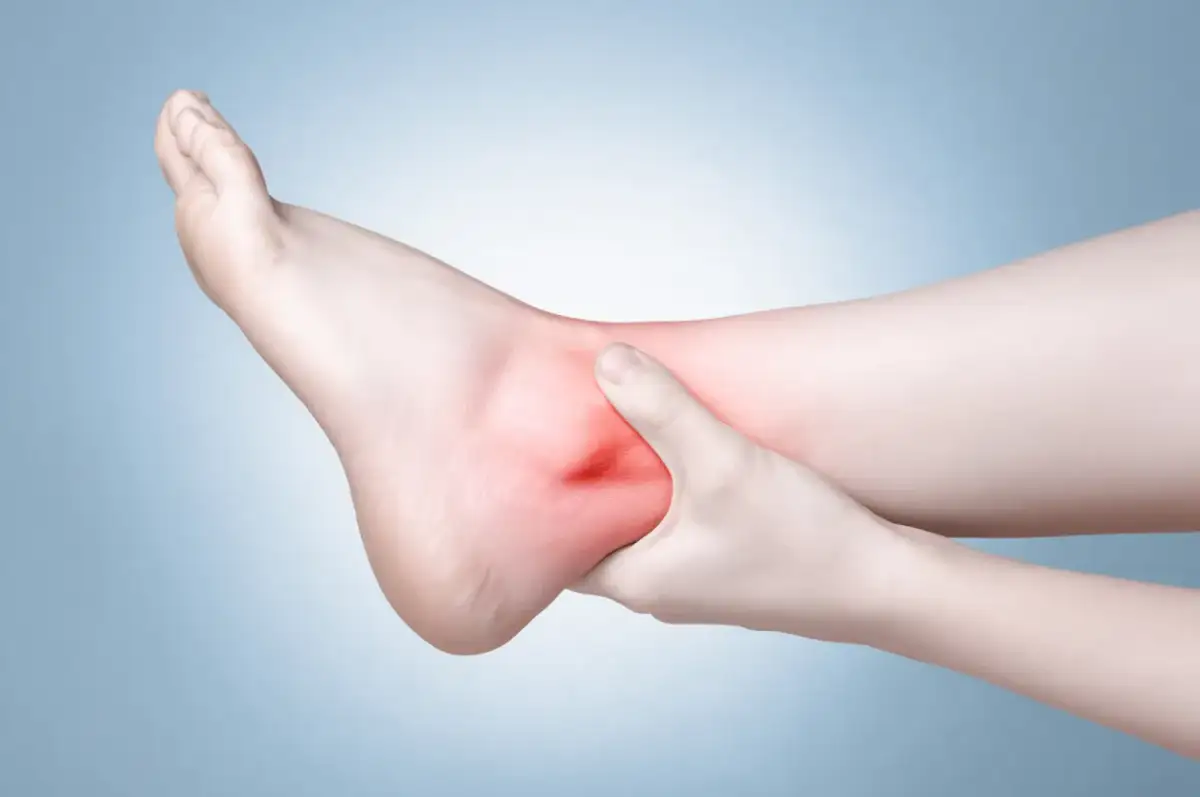

3. Błyskawiczna opuchlizna i narastający obrzęk

Opuchlizna, czyli obrzęk, pojawia się bardzo szybko po urazie, często niemal natychmiast, i może być naprawdę znaczna. Jest to naturalna reakcja organizmu na uszkodzenie tkanek miękkich, takich jak torebka stawowa i więzadła, oraz na wewnętrzne krwawienie. Im szybciej i bardziej narasta obrzęk, tym poważniejszy zazwyczaj jest uraz.

4. Krwiak i zasinienie skąd się biorą?

Zasinienie i krwiak pojawiają się zazwyczaj nieco później niż ból i opuchlizna, stopniowo rozwijając się wokół miejsca urazu. Są one wynikiem wewnętrznego krwawienia, spowodowanego uszkodzeniem drobnych naczyń krwionośnych w okolicy stawu. Ich pojawienie się jest kolejnym dowodem na rozległość urazu.